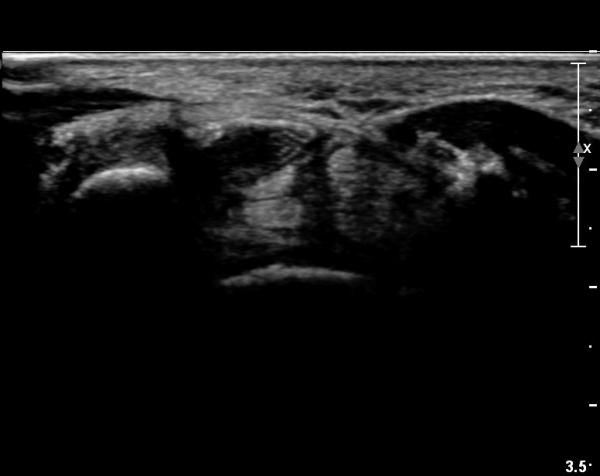

ÃÊÀ½ÆÄ ¼Ò°ß :  ¼Õ¸ñ±ÙÀ§ºÎ Ⱦ´Ü¸é°Ë»ç¿¡¼­ ¼Õ¸ñ±¼±Ù°Ç(FCR)°ú Ç¥Ãþ ¼Õ°¡¶ô ±ÁÈû±Ù(FDS) »çÀÌ¿¡

Á¤Á߽ŰæÀÌ Á¤»óÀûÀÎ ¾ç»óÀ¸·Î º¸ÀÓ(»çÁø 1).

Å½ÃËÀÚ¸¦ ¸»´ÜÀ¸·Î À̵¿ÇÏÀÚ  Á¤Áß½Å굥 ¿äÃø ÀϺΰ¡ Àú¿¡ÄÚ Á¾±«·Î °üÂûµÊ(»çÁø 2).

ÀÌ·± ¸ð½ÀÀº ¼Õ¸ñÀÇ ¿ù»ó°ñ ºÎÀ§(»çÁø 3, 4)¸¦ Áö³ª ¼ö±Ù°ü ±ÙÀ§ºÎ ±îÁö À̾îÁü(»çÁø 5).